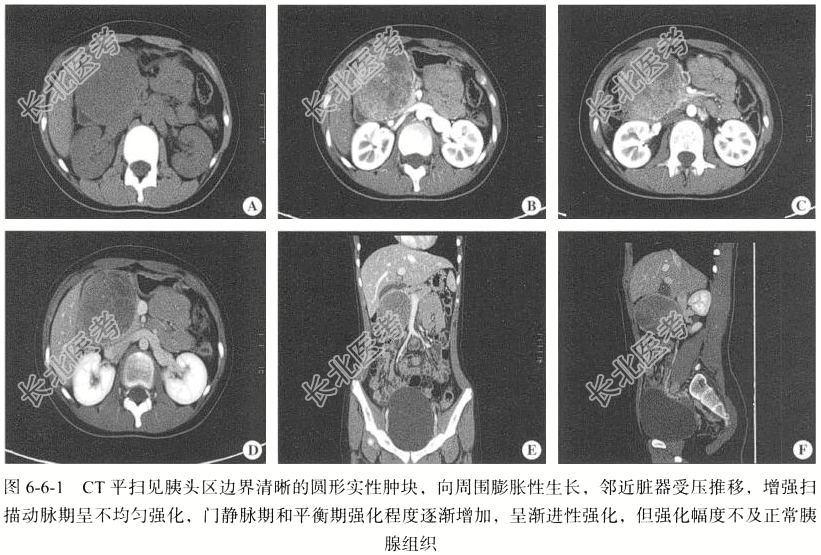

【影像图片】见图6-6-1。

【手术所见】十二指肠中段、胰头部见一类圆形肿瘤,约为8cm×8cm。

【病理所见】结合HE形态学及免疫表型结果,符合胰腺实性假乳头状肿瘤(图6-6-2),肿物大小约为7cm×6cm×4cm,肿物位于十二指肠下方胰腺内,两侧肠切缘未见肿瘤累及,周围淋巴结未见肿瘤转移(0/1)。免疫组化结果:AE1/AE3(-),CD68(少+),CAM5.2(-),CK8(+),CD10(+),Vim(+),β-catenin(+),Syn(-),CgA(-),CD56(+),Ki-67(+8%),S-100(-),SMA(-),CD34(血管+)。

【病理诊断】胰腺实性假乳头状瘤。